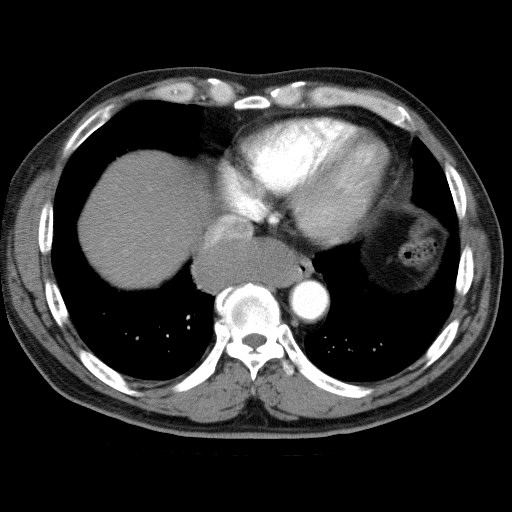

69¼¼ ³²È¯ DM,HTN °ú°Å·Â ÀÖ´ø ȯÀÚ·Î ³»¿ø 10³âÀüºÎÅÍÀÇ right pleural chest pain À» ÁÖ¼Ò·Î ³»¿øÇÑ È¯ÀÚÀÇ CxR ¹× Chest CTÀÔ´Ï´Ù.